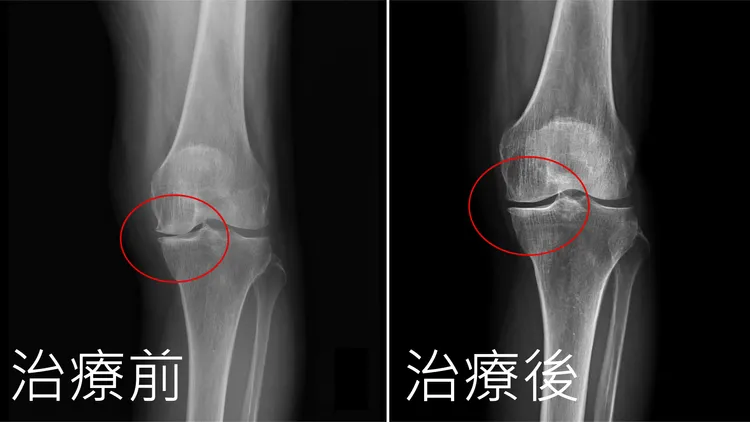

「自體免疫細胞治療」治療膝關節前後對照圖。亞大附醫提供

只是考量患者年紀大排斥動刀,因此評估後,建議採用「自體免疫細胞治療」(Autologous Immune Cells;簡稱AI Cells)新技術,透過先抽取自身血液,經過血液細胞純化技術(PCP)後,將取出的高濃度細胞萃取液注射到患部,不僅達到抗發炎效果,還能促進軟骨分化以及膠原蛋白的生成等優點,更加有效修復受損的關節腔,這項由國人自主研究的醫療成果,目前也已經取得美國FDA 二類醫材證,此國際認證有助於推動多國臨床。